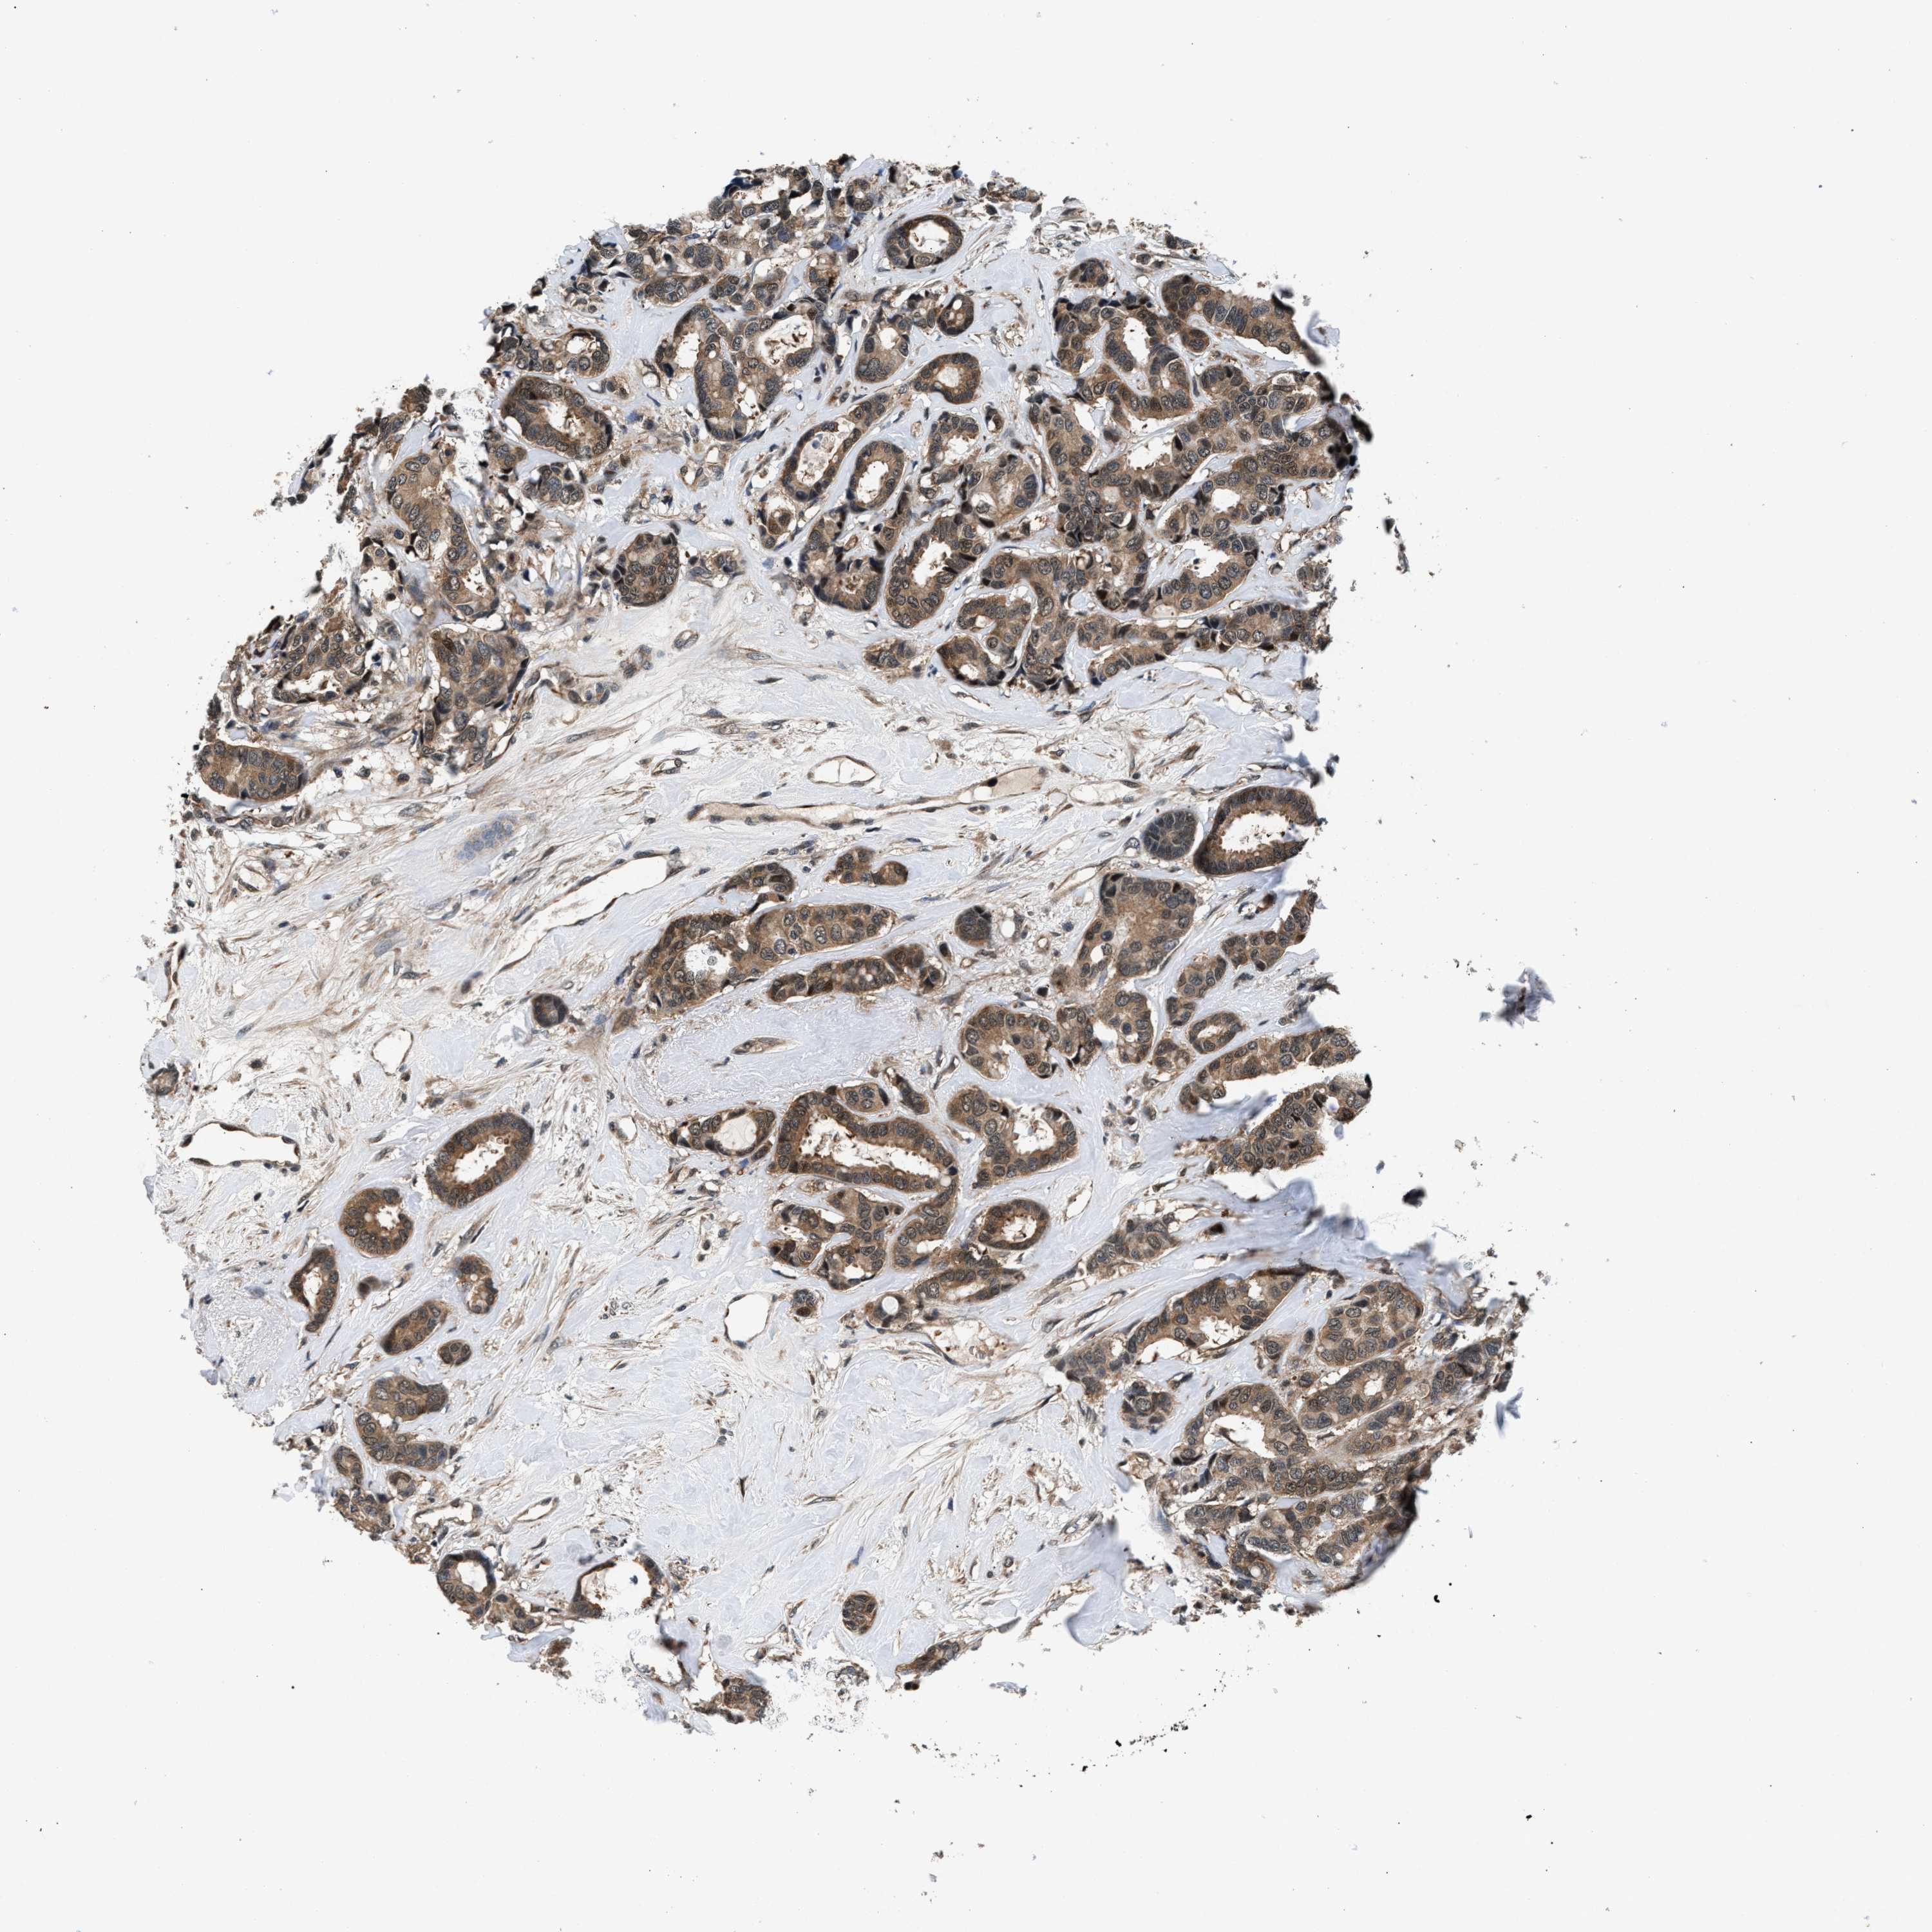

CANCER BREAST CANCER Show tissue menu

BRCA TCGA BRCA VALIDATION PROTEIN EXPRESSION